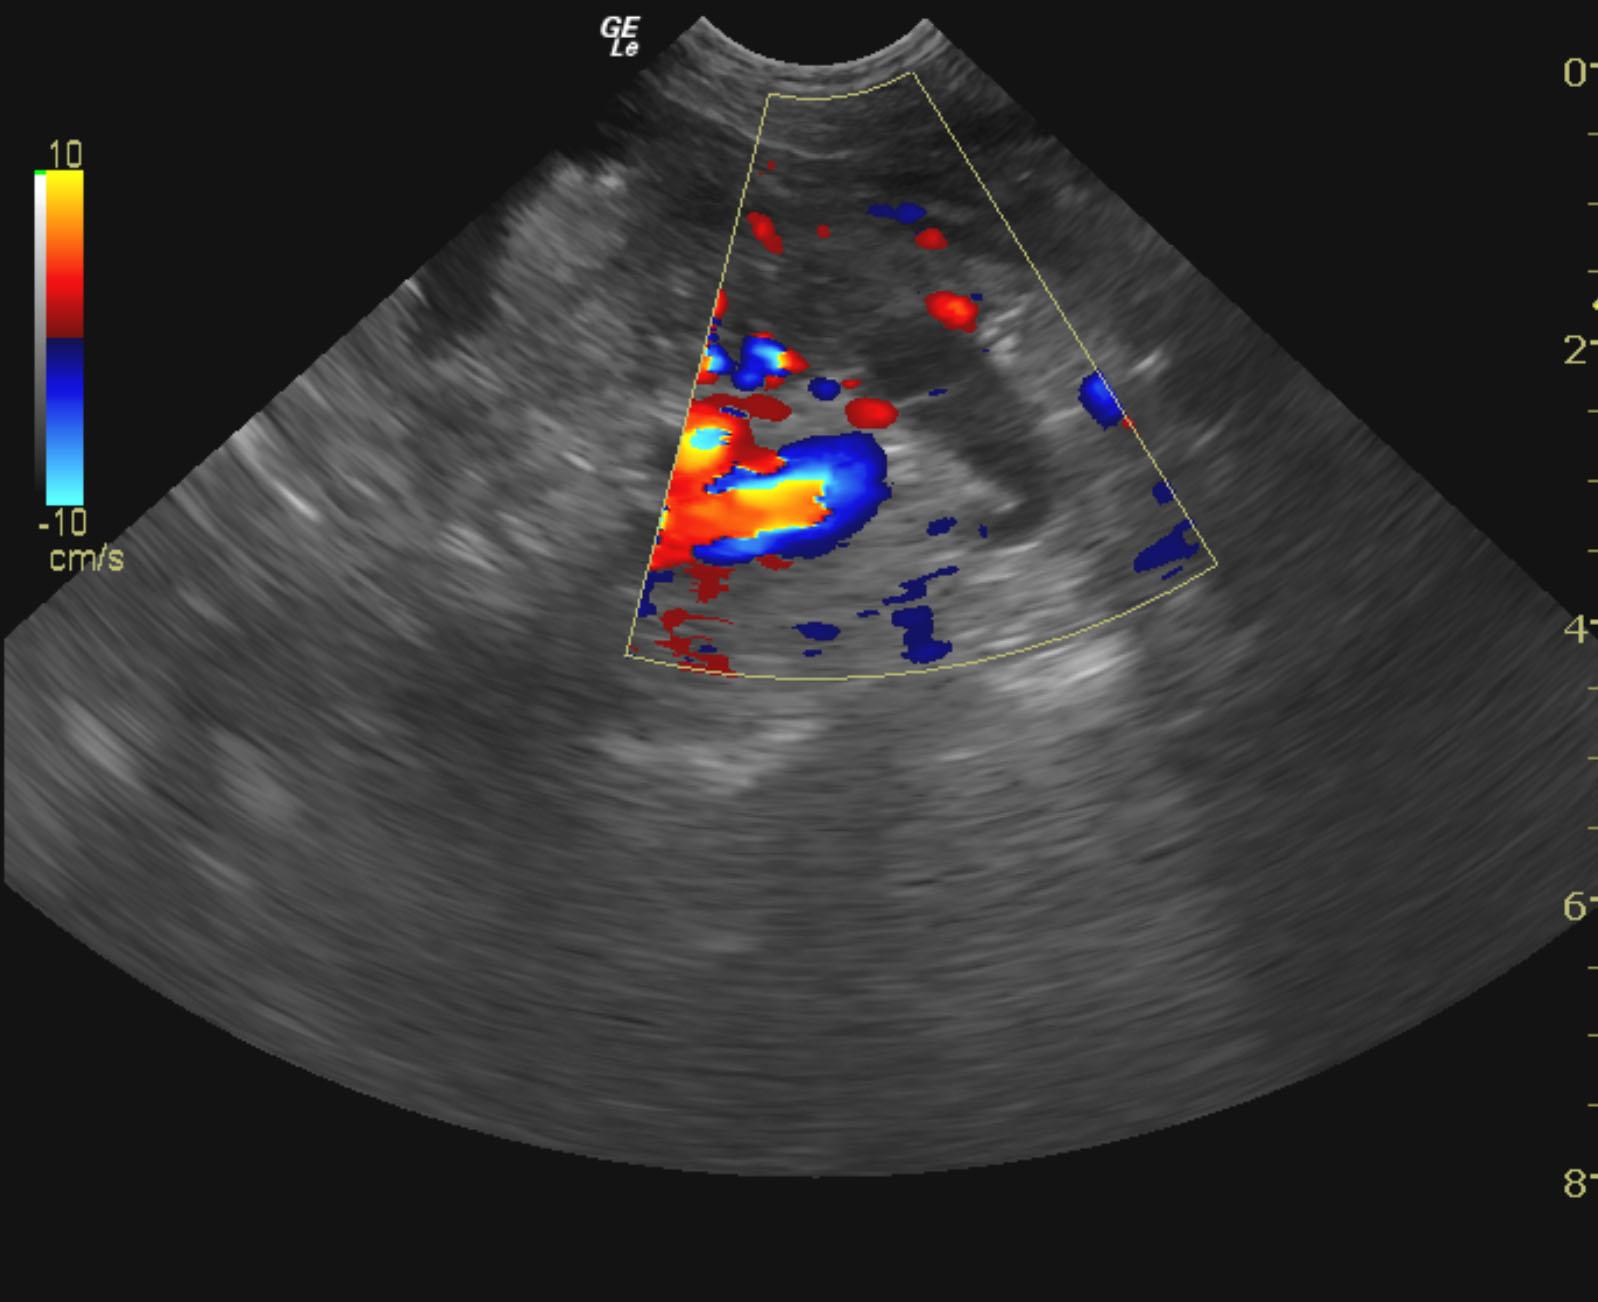

A 10-year-old SF American Eskimo with a history of bladder transitional cell carcinoma that had been stented, chronic renal insufficiency, hydronephrosis, and hydroureter, was presented for evaluation. CBC showed anemia (14%).